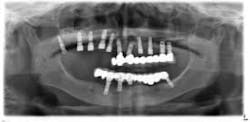

Under local anesthesia, a full thickness flap was elevated from the upper right to upper left posterior segments. Using a piezoelectric handpiece, a buccal window hinge osteotomy was elevated in the maxillary right posterior region. A mixture of DFDBA, anorganic bovine bone, and PRF was placed. A collagen membrane was used to cover the buccal window. Simultaneously, two puros J-block allografts were secured in the 5 to 7 and 10 to 12 region with stainless steel screws (1.6 x 8 mm screws). A mixture of DFDBA, anorganic bovine bone and PRF was placed over each area and covered with PRF sheet and a collagen membrane. Primary closure was obtained with CV-5 Goretex sutures. Healing was uneventful. After six months of healing, six straight implants were placed in sites 3, 4, 5, 6, 11, and 12. Healing abutments were placed at stage I. Healing was uneventful. After four months of healing, six custom abutments were fabricated by his dentist and cover screws were placed on implants 8 and 9 and converted into pontics.

Removing the implants would have created a large buccal defect, which would have created elongated pontics in the maxillary anterior region. The prosthesis was completed, and the patient is stable and highly appreciative of her ability to smile and chew.

Case 2: Sinus lift, bone graft, PRP, and after healing implant placement